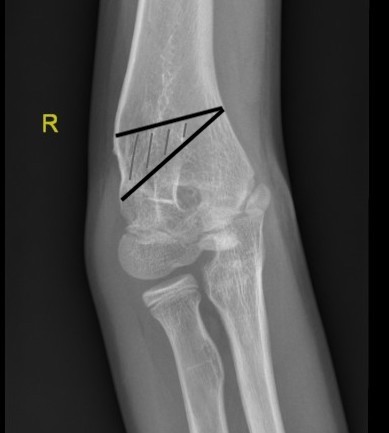

AP X-ray

Baumann's Angle

Technique

- angle between longitudinal axis humerus and capitellar physis

- should equal uninjured side

- 75o normal

Cubitus varus

- varus malposition > 81°

Cubitus valgus

- < 70o